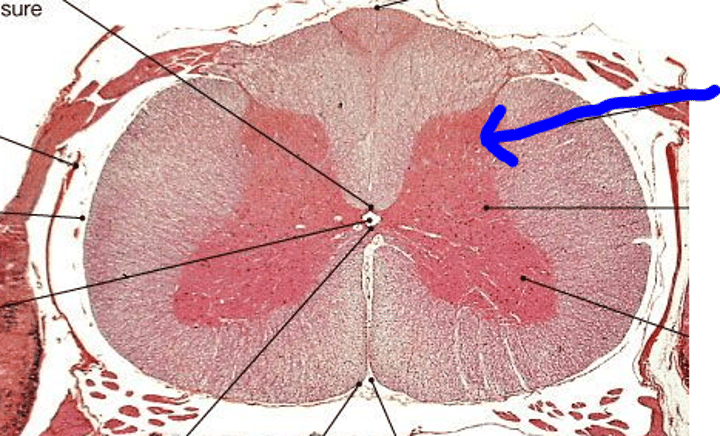

Spinal Cord Slide - anterior gray horn

Spinal Cord Slide - posterior gray horn

Spinal Cord Slide - anterior white column

Spinal Cord Slide - lateral white column

Spinal Cord Slide - posterior white column

Spinal Cord Slide - ventral root

Spinal Cord Slide - motor neurons

Spinal Cord Slide - dorsal root

Spinal Cord Slide - dorsal root ganglion

Spinal Cord Slide - unipolar neurons

Spinal Cord Slide - pia mater

Spinal Cord Slide - dura mater

Spinal Cord Slide - anterior median fissure

Spinal Cord Slide - posterior median sulcus